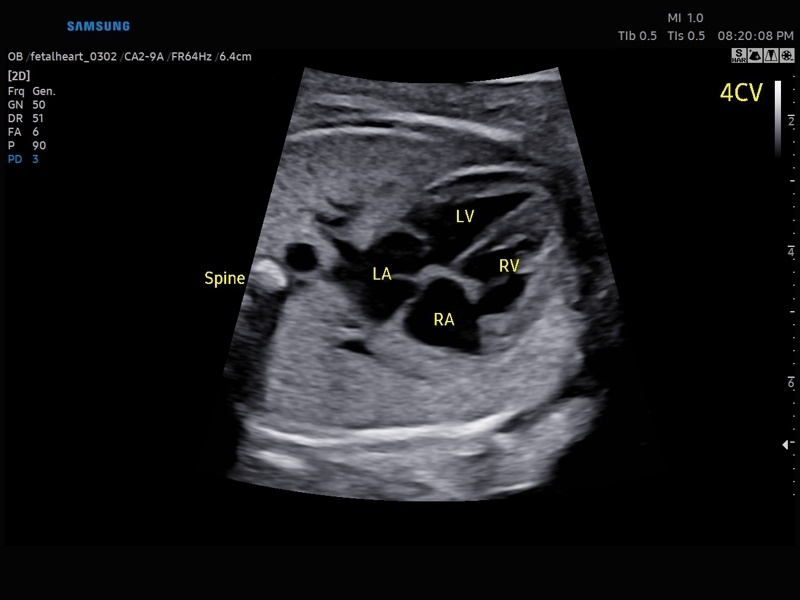

Ультразвуковой сканер V8-RUS является экспертным классом (премиальный уровень) и производится компанией Samsung Medison. Сканер V8 обеспечивает превосходное качество изображения благодаря использованию технологии Crystal Architecture™, которая включает в себя передовое аппаратное обеспечение, монокристальную технологию изготовления датчиков и сложную программную обработку ультразвуковых лучей.

Samsung Medison V8 представляет собой современную ультразвуковую систему, в которой воплощен многолетний опыт компании Samsung в создании эргономичного и интеллектуального диагностического оборудования. Система оснащена передовыми инструментами автоматизации, которые значительно упрощают рабочий процесс и повышают эффективность исследований.

Система Samsung Medison V8 обеспечивает высококачественную диагностику в различных областях медицины:

• Абдоминальные исследования

• Акушерство и гинекология

• Кардиология

• Сердце плода:измерения в В-режиме (отношение площади сердца и грудной клетки), измерения в М-режиме (толщина межжелудочковой перегородки в диастолу, конечнодиастолический размер левого желудочка, толщина задней стенки левого желудочка в диастолу, толщина межжелудочковой перегородки в систолу, размер левого желудочка в систолу, толщина задней стенки левого желудочка в систолу, внутренний размер правого желудочка в диастолу), измерения в режиме спектрального допплера (легочный ствол, артериальный проток, нижняя полая вена, венозный проток, восходящая аорта, нисходящая аорта, трансмитральный кровоток, митральная регургитация, трикуспидальный кровоток, трикуспидальная регургитация, индекс преднагрузки, ЧСС).